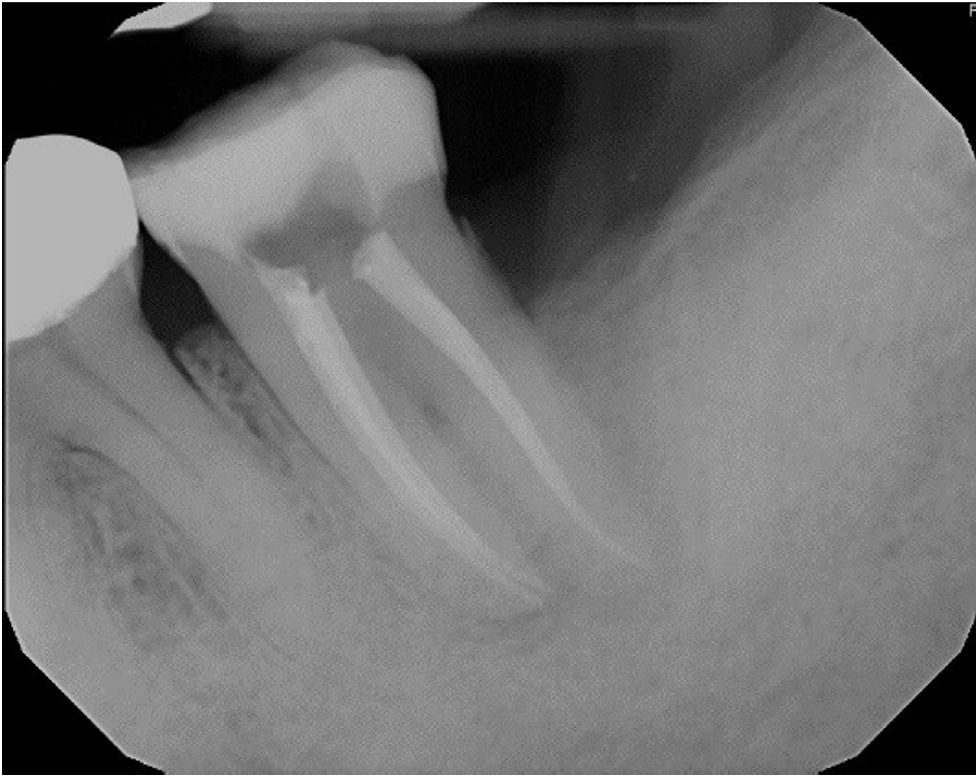

Radiographically, a “J-shaped” lesion was observed along the distal root of #18 (Figure 1), suggestive of a primary endodontic lesion with secondary periodontal involvement. A radiopaque fragment, consistent with a cemental tear, was identified along the distal root surface (Figure 1).

Figure 1.

“J-shaped” lesion observed along the distal root of #18 (yellow arrow). A radiopaque fragment, consistent with a cemental tear, was identified along the distal root surface (red arrow).

rde-2025-50-e31f1.jpg

Figure 1. “J-shaped” lesion observed along the distal root of #18 (yellow arrow). A radiopaque fragment, consistent with a cemental tear, was identified along the distal root surface (red arrow).